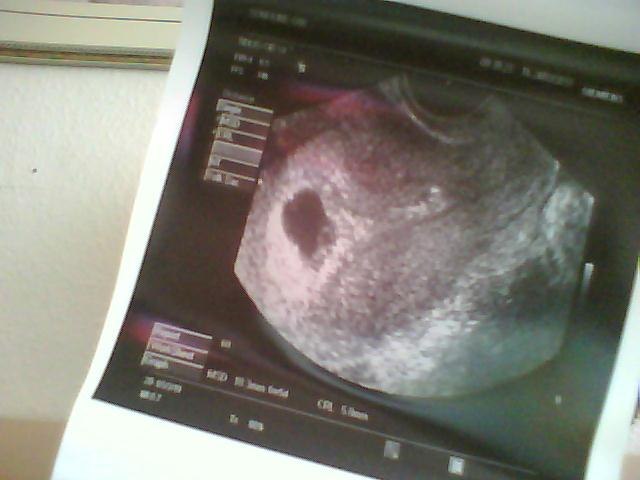

Vores bebs har det fantastisk Hjertet slog bare derud af

Jeg er 6+5, og sagde gynækologen også jeg var Termin 12. nov

Scannes igen om 14dage, og se om baby er voksede

Vedhæftede fotos (klik for at se i fuld størrelse)

Skøn lille blyp der ligger derinde.